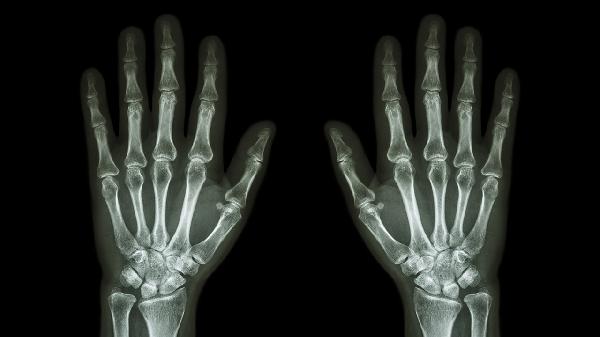

手指关节滑膜增厚2mm是否严重需结合具体病因判断,多数情况下属于轻度异常,少数可能与关节炎等疾病相关。

滑膜增厚2mm常见于关节慢性劳损或轻微炎症反应,通常表现为局部轻微肿胀、活动时偶发酸胀感。这类情况多与长期重复性手部动作、受凉或轻微外伤有关,通过减少关节负荷、热敷或短期使用非甾体抗炎药如布洛芬缓释胶囊、双氯芬酸钠肠溶片等可缓解。日常注意避免手指过度屈伸动作,使用护具分担压力,多数预后良好。

若滑膜增厚伴随持续疼痛、晨僵超过30分钟或关节变形,需警惕类风湿关节炎、痛风性关节炎等病理因素。此时增厚的滑膜可能伴随血管翳形成,导致软骨侵蚀。需完善类风湿因子、抗CCP抗体或尿酸检测,必要时行关节腔穿刺抽液分析。治疗需遵医嘱使用甲氨蝶呤片、来氟米特片等抗风湿药,或苯溴马隆片等降尿酸药物,配合超声引导下滑膜穿刺治疗。

建议定期复查关节超声观察滑膜变化,避免提拉重物或冷水刺激。饮食上增加深海鱼类、坚果等抗炎食物摄入,肥胖者需控制体重减轻关节负担。若出现关节发热、夜间痛醒或功能受限,应及时至风湿免疫科就诊。